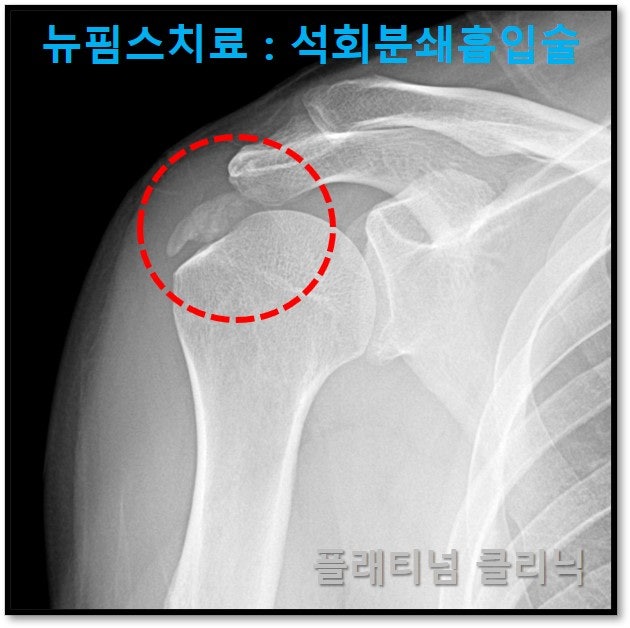

뉴핌스치료: 석회분쇄흡입술 을 통해 석회를 근본적으로 제거하여 석회성 건염의 고통에서 벗어날 수 있습니다. 보여드릴 케이스는 45세 남자환자로 2년간 석회성 건염으로 고통받으신 환자분 입니다. 석회성 건염을 진단받고 충격파, 주사치료를 했으나 잠깐 좋아지는 듯 하다 통증이 재발되고 이것이 반복되면서 가동범위 제한까지 와서 일상적인 생활이 안되어서 저한테 오신 분이었습니다. 현재 수술할 수 있는 상황이 되지 않아 비수술적으로 치료 하고자 한다고 하셨습니다.

석회를 근본적으로 제거하기 위해 뉴핌스:석회분쇄흡입술을 시행하였고 유착성관절낭염에 대해서도 뉴핌스:관절유착박리술도 같이 시행하였습니다. (아래링크에서 참고하시면 됩니다.) https://blog.naver.com/9690067/222705294825